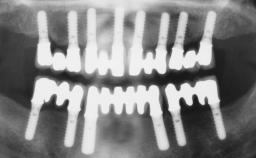

A 35-year-old Caucasian female presenting with advanced periodontal disease involving both the maxillary and the mandibular dentition was referred for evaluation. The patient, a non-smoker in good general health, requested treatment for recurrent periodontal abscesses, tooth mobility, and discomfort during chewing, as well as restoration of her missing teeth with a fixed prosthesis to improve mastication and esthetics. All residual maxillary teeth exhibited plaque deposits, deep pockets, bleeding on probing, and class III mobility and were evaluated as hopeless. All residual mandibular teeth except tooth 37 could be maintained after periodontal therapy.

| # of Implants | 8 |

| Bone Augmentation | Horizontal|Staged|Vertical |

| Augmentation Materials | Autogenous block(s) |